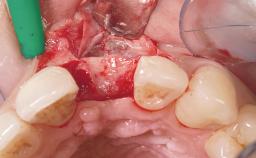

A 29-year-old female patient presented for treatment to replace the upper left central incisor tooth with an implant- supported restoration. The tooth had been intermittently symptomatic for the previous 12 months. The tooth had originally suffered trauma about 15 years previously. Several endodontic treatments had been performed, including an apicectomy procedure to retain the tooth. The patient was healthy and a non-smoker. She had reasonable expectations in regard to esthetic outcomes and the risk of marginal tissue recession following treatment. At medium smile, the gingival margins of the upper teeth were visible, with a display of 3 to 4 mm of the gingival margins. Gingival recession of tooth 21 and a discrepancy in the gingival levels between teeth 11 and 21 was observable during normal speech and smile.

Placement Protocol Immediate implant placement

Socket Integrity Damage to one or more bone walls

Bone Volume Damage to one or more socket walls